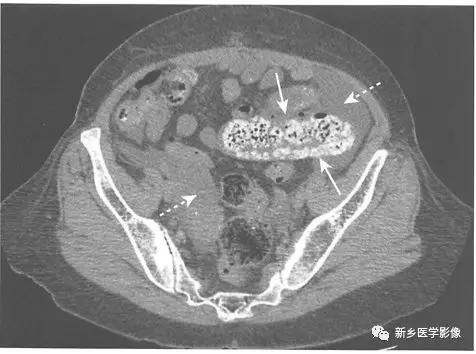

4、在CT上辨识大肠梗阻

CT可用来确定梗阻原因、评估是否存在腹腔游离气体以及明确相关并发症,如肝脏或淋巴结转移等。

在梗阻部位近端大肠肠腔扩张,在梗阻部位远端肠腔直径恢复正常。

梗阻处通常是结肠癌造成,在CT上表现为软组织肿块,累及大肠的疝也很容易在CT上显示。